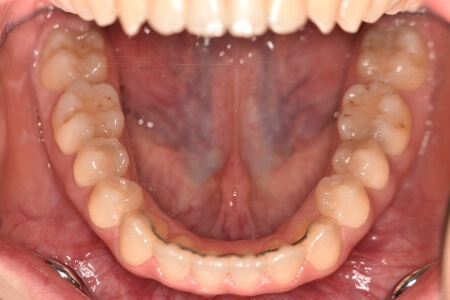

動的治療終了時

症例 症例 症例 症例

治療としては、上顎第一小臼歯を抜歯の上、セルフライゲーションブラケット装置(デーモンシステム)とマウスピース型矯正装置(インビザライン)で配列を行いました。顎間ゴムの協力もあり、開咬がきれいに改善されました。

この際、上顎に歯科矯正用アンカースクリューを設置し上顎前歯部後退時の土台としました。

治療期間としては、2年8か月でした。